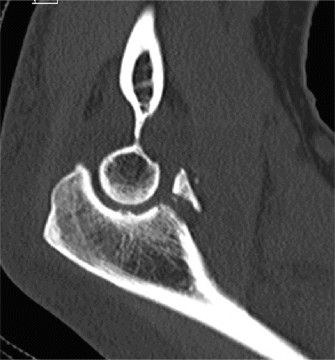

Computed Tomography (CT) Scan:

- Given the post-reduction instability and the suspected coronoid fracture, a CT scan of the elbow was obtained to delineate the fracture morphology, displacement, and identify any other subtle bony injuries.

- The CT confirmed a large, comminuted fracture of the anteromedial facet of the coronoid process (O'Driscoll Type III), involving more than 50% of the coronoid height. This fragment was significantly displaced and rotated.

- There was no associated radial head or olecranon fracture, which helped differentiate from a terrible triad.

- The CT also provided detailed assessment of the trochlear integrity and the overall joint alignment, confirming the posteromedial displacement pattern.